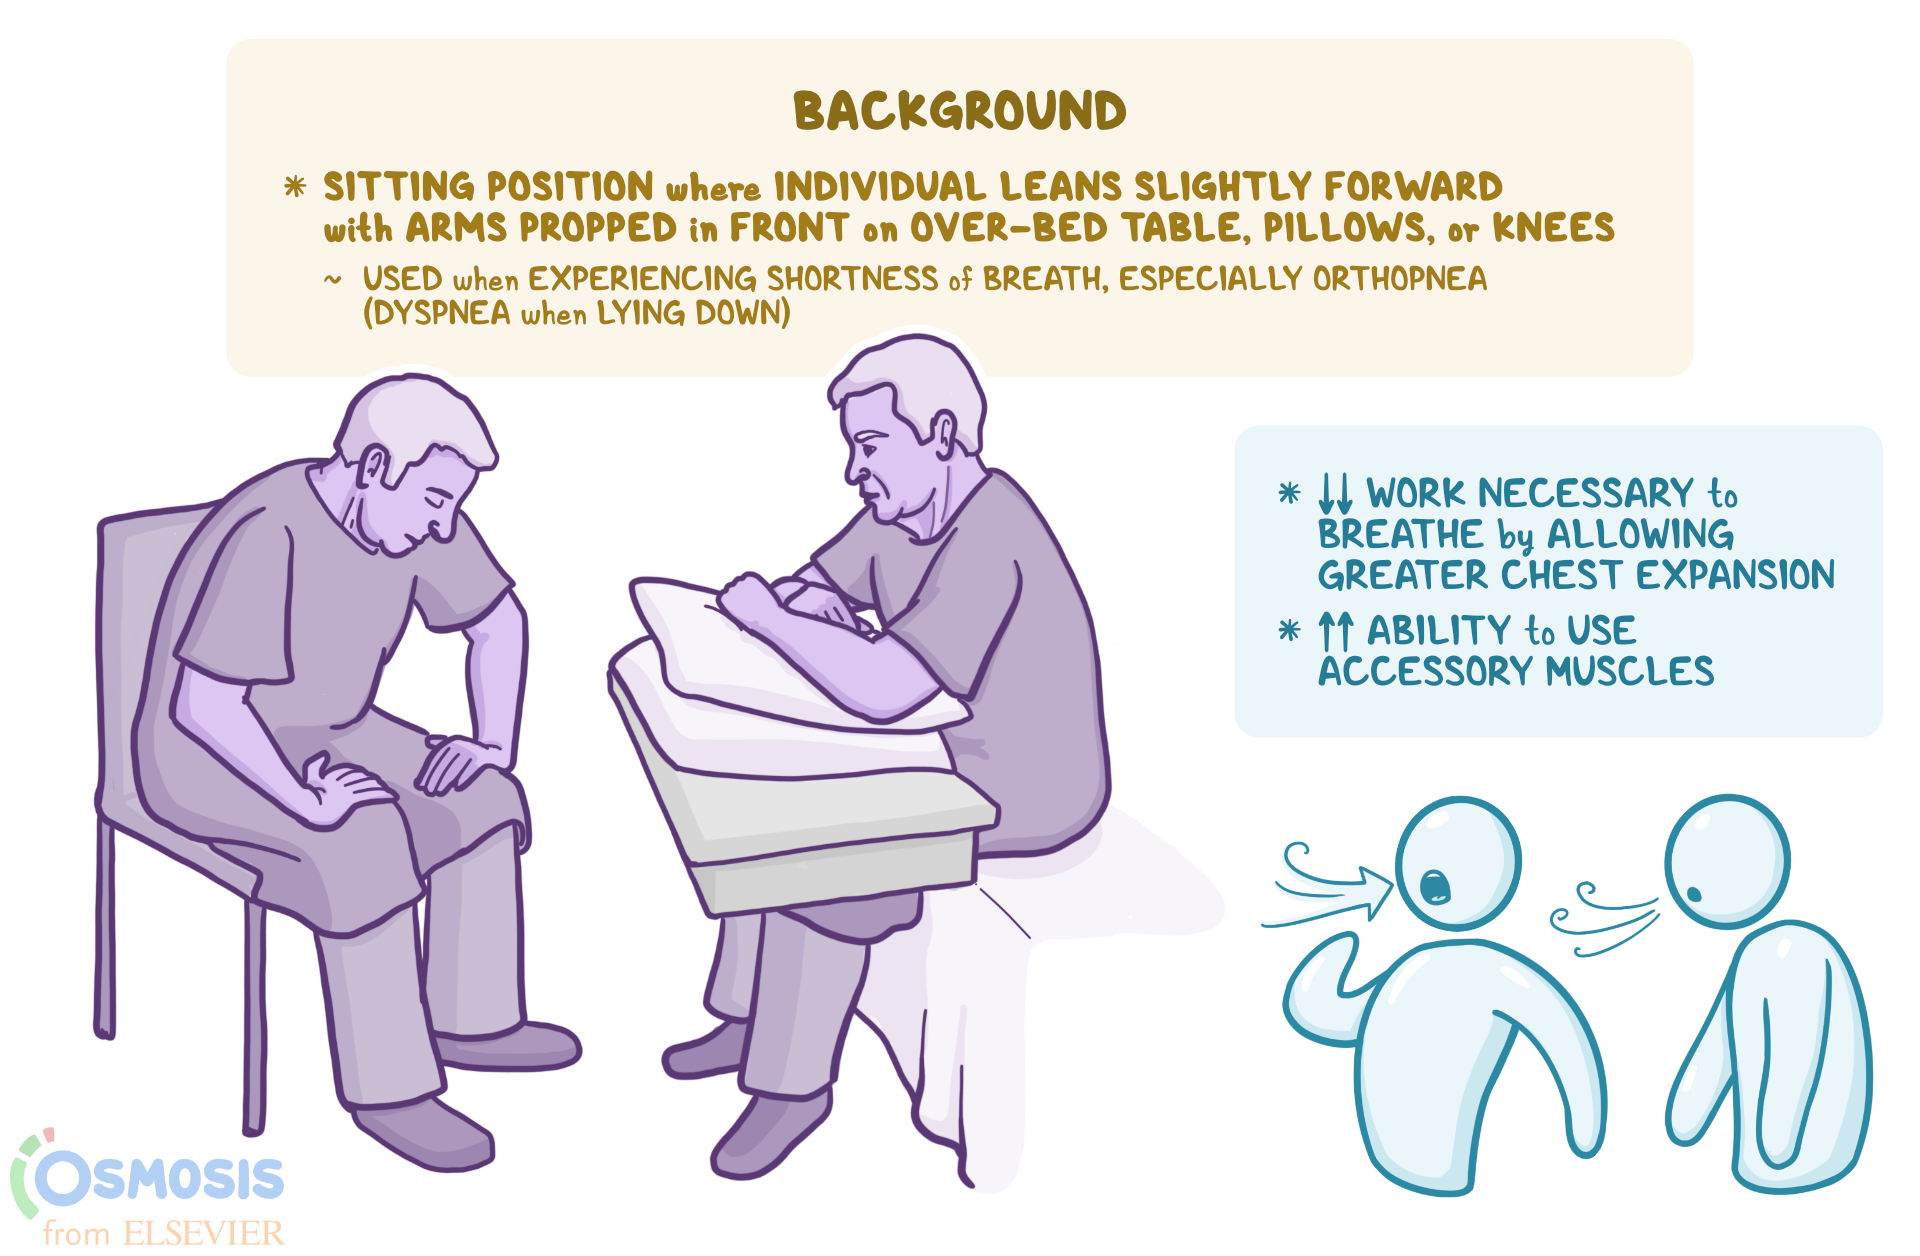

[desc-10] [desc-11]